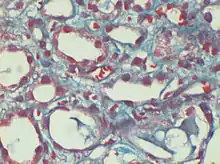

Dilated peri-tubular capillaries filled with sickled RBCs, original Gomori's trichrome stain, × 400. Kanodia et al. Diagnostic Pathology 2008.[1]